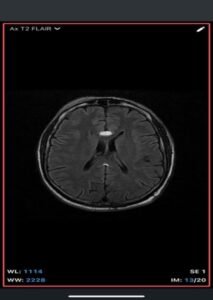

- MRI

- T1-weighted: Hyperintense (fat signal).

- T2-weighted: Variable, usually hyperintense; may show chemical shift artifacts.

- Fat-suppressed sequences: Complete signal suppression confirms fat composition.

- Post-contrast: No enhancement.

- Often associated with:

- Corpus callosum agenesis/dysgenesis